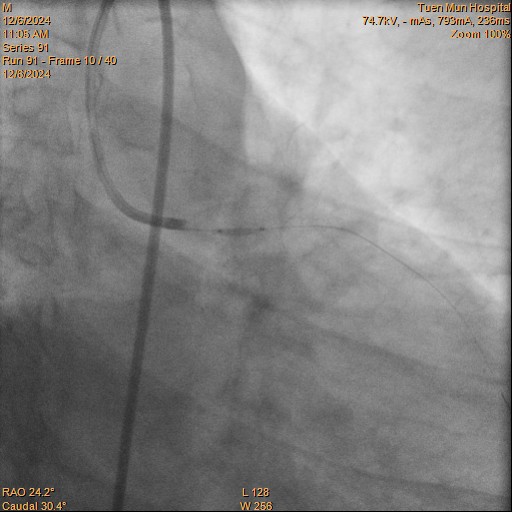

LAD dilated with 1.5 balloon.IVUS confirmed wire in true lumen.o-pLAD stented with Xience 2.5/26.IVUS showed stent protruded into LMS, decided for stenting to LMS.

Plan for Xience 3.5/8 into LM, but stent not long enough. So plan to switch for longer stent 3.5/12.But stent dislodged while being retrieved out.

So the 3.5/8 stent was serially dilated with 1.5, 2.25 & 3.0 NC with stent boost guidance. POT done at LMS with NC 4.0/6 at 22atm. oLAD dilated with stent balloon 3.5/8 at 14atm.